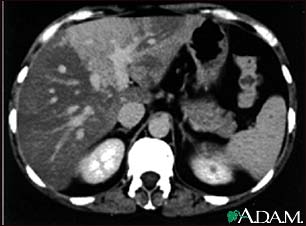

Liver with disproportional fattening, CT scan

A CT scan of the upper abdomen showing disproportional steatosis (fattening) of the liver.